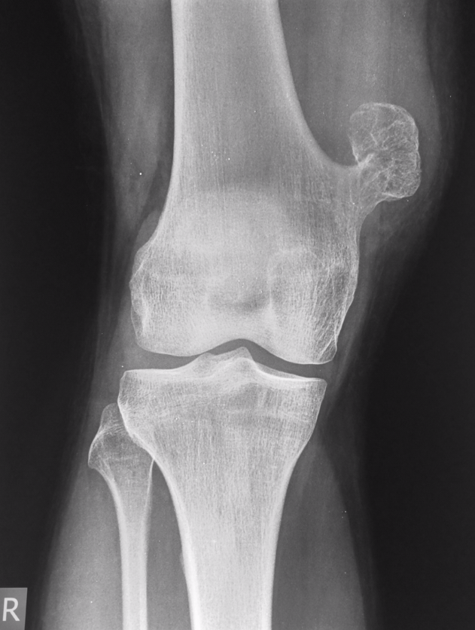

Little League elbow

• avulsion frature of the medial epicondyle